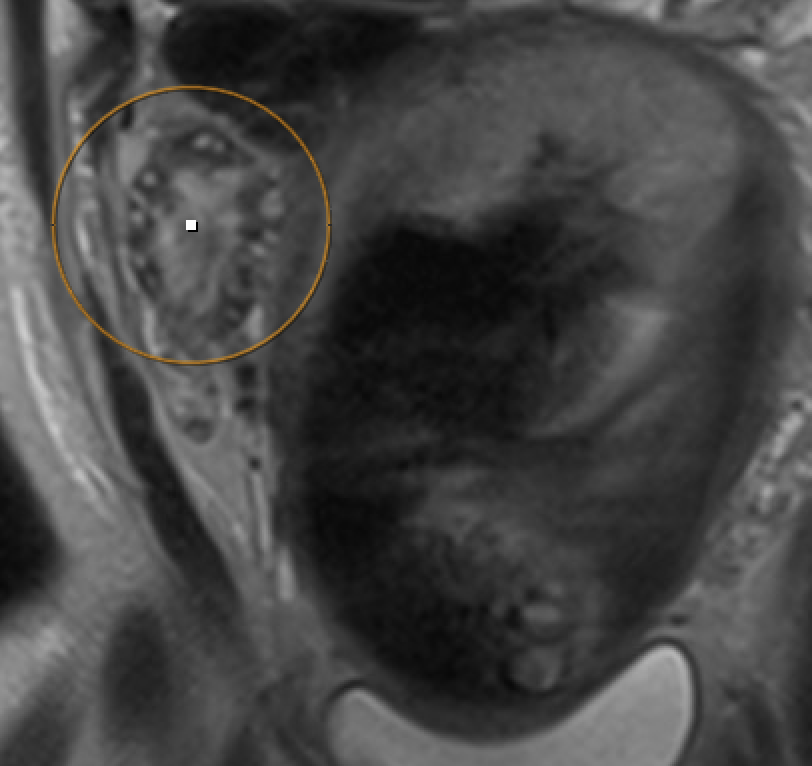

Ovarian torsion (pregnancy) Enlarged ovary with peripheral follicles and stromal edema on T2W. Pelvic ascites. Compare with contralateral ovary. Whirlpool sign of twisted pedicle

MRI showing ovarian torsion with enlarged ovary, peripheral follicles, and stromal edema on T2W

Ovarian torsion: enlarged ovary, peripheral follicles, stromal edema